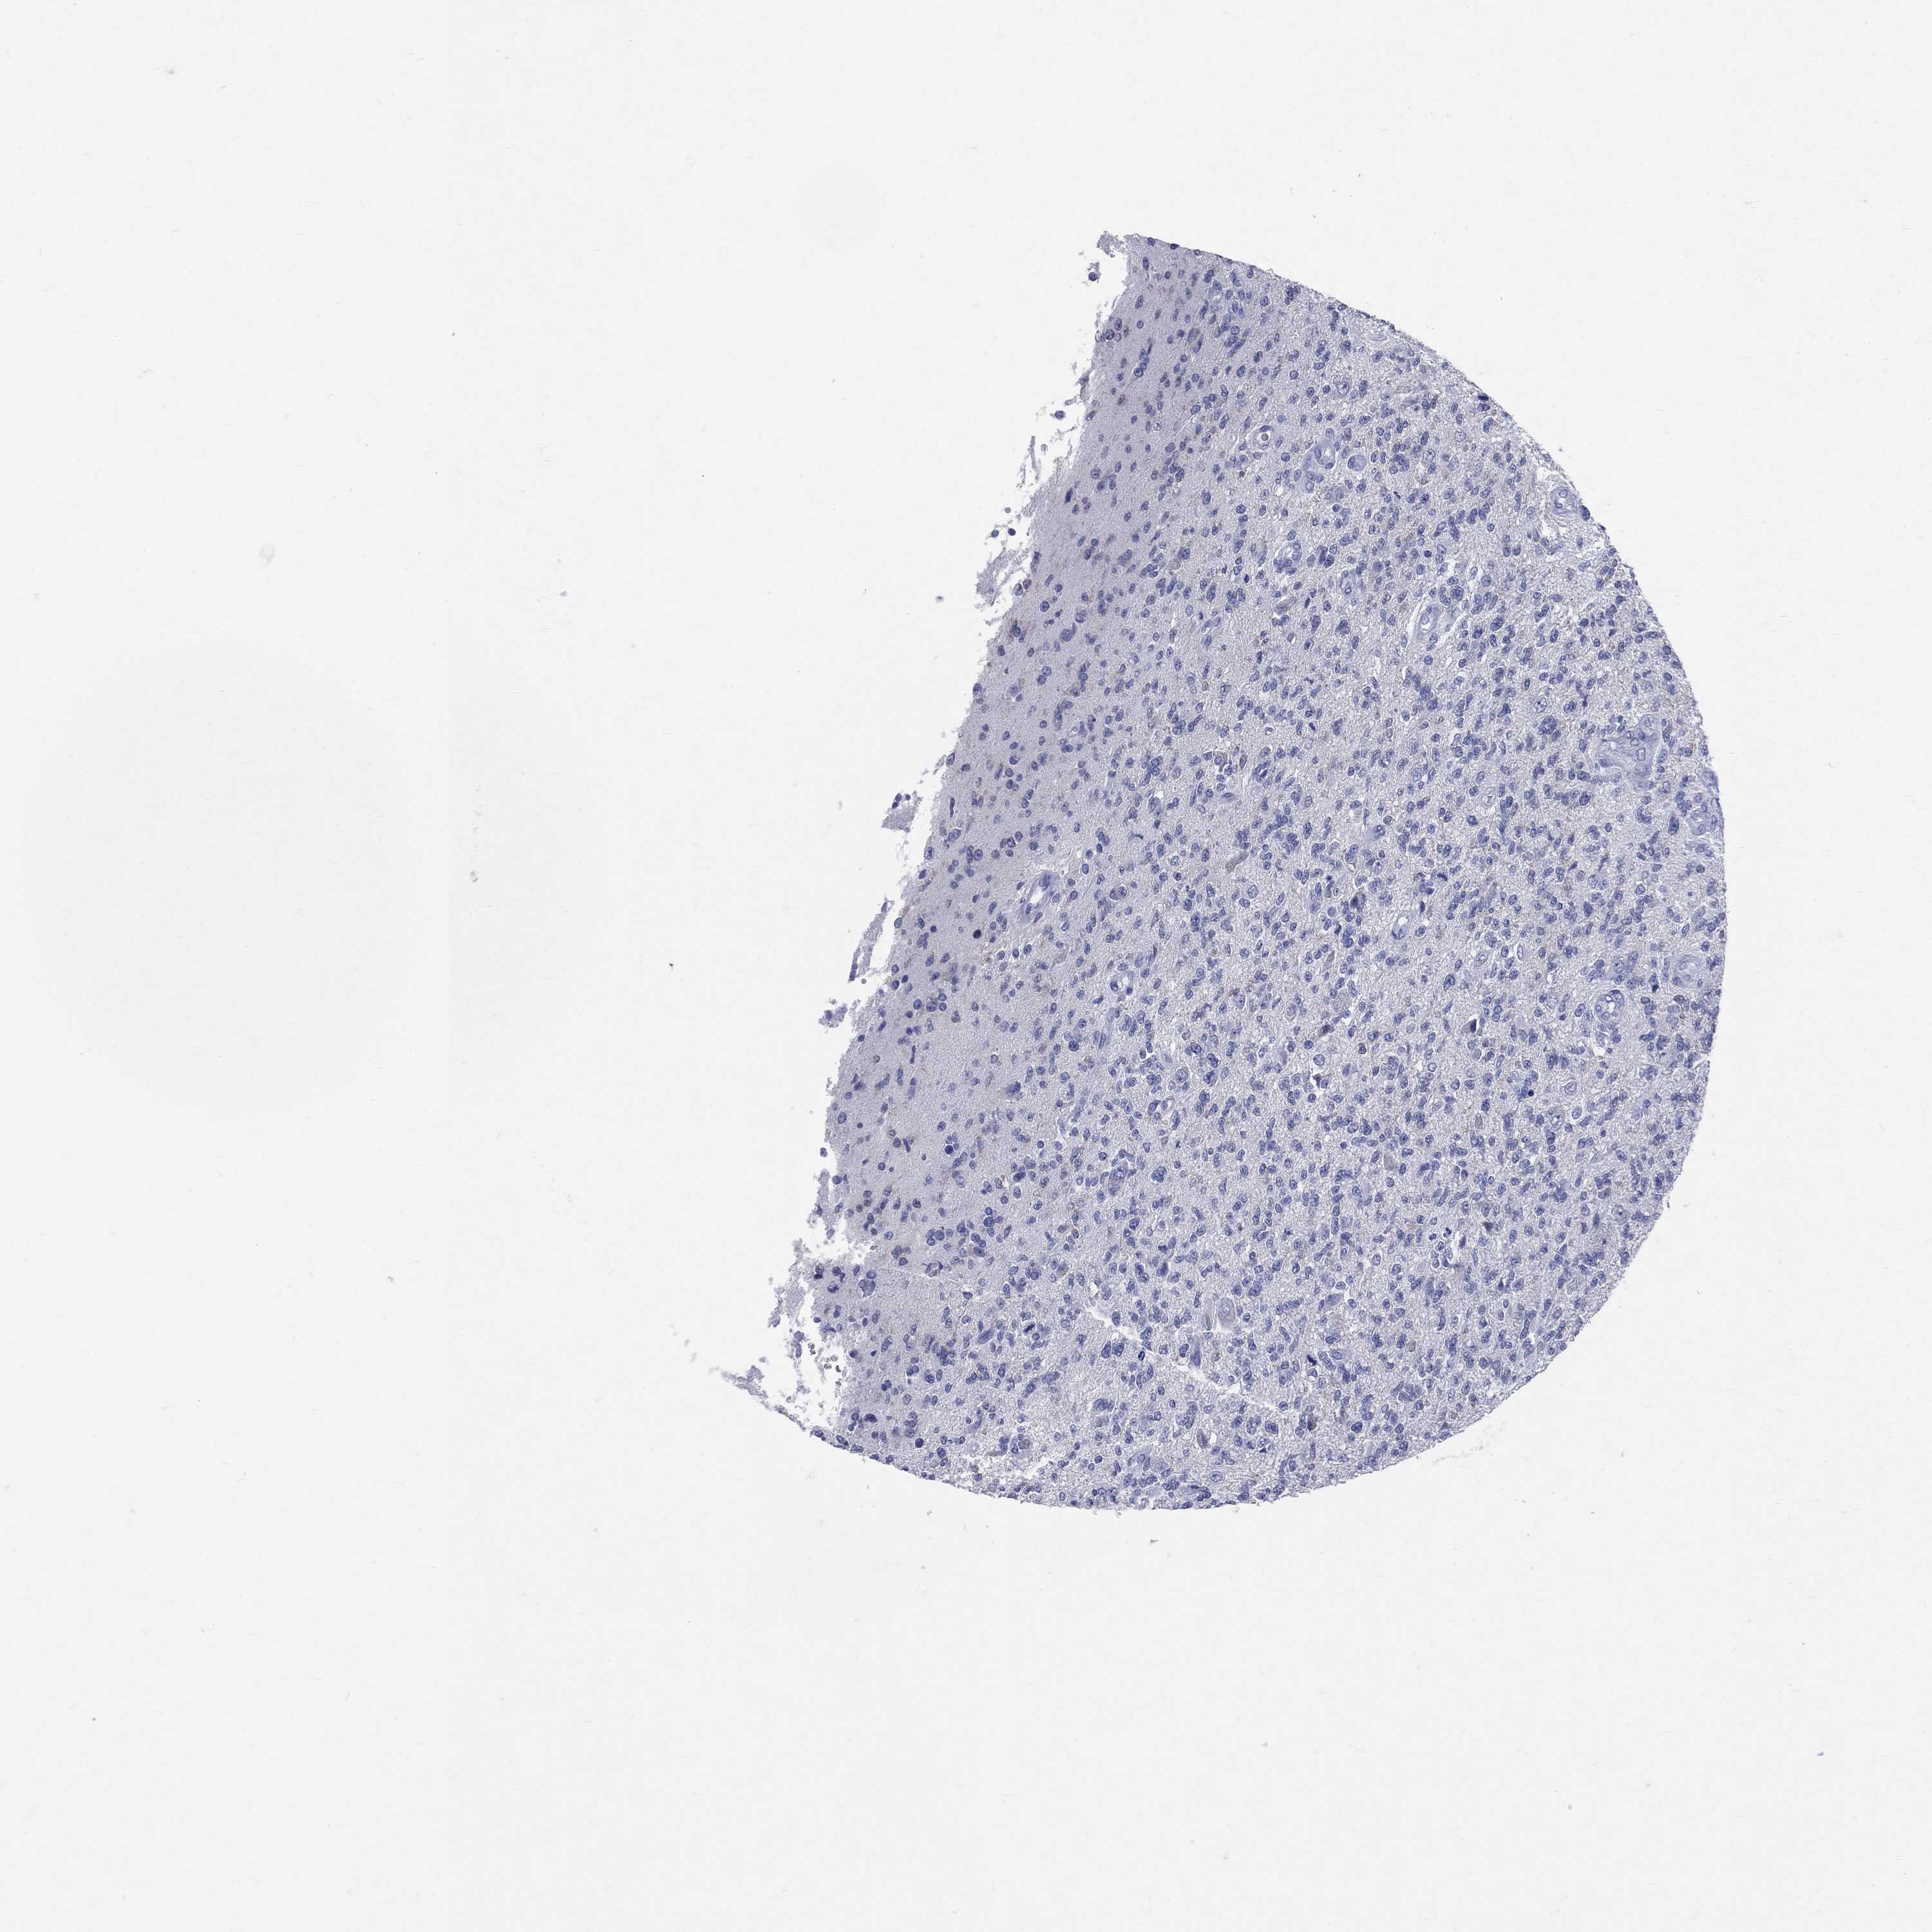

GLIOMA - Protein expressioni

A mouse-over function shows sample information and annotation data. Click on an image to view it in a full screen mode. Samples can be filtered based on level of antibody staining by selecting one or several of the following categories: high, medium, low and not detected. The assay and annotation is described here.

Antibody stainingi

Antibody staining in the annotated cell types in the current human tissue is reported as not detected, low, medium, or high, based on conventional immunohistochemistry profiling in selected tissues. This score is based on the combination of the staining intensity and fraction of stained cells.

Each image is clickable and will lead to virtual microscopy that enables deeper exploration of all samples and also displays staining intensity scores, fraction scores and subcellular localization as well as patient and tissue information for each sample.

Antibody HPA070355

Antibody HPA078303

Staining

High

Medium

Low

Not detected

Intensity

Strong

Moderate

Weak

Negative

Quantity

>75%

75%-25%

<25%

None

Location

Nuclear

Cytoplasmic/membranous

Cytoplasmic/membranous,nuclear

Glioma, malignant, Low grade

Glioma, malignant, High grade